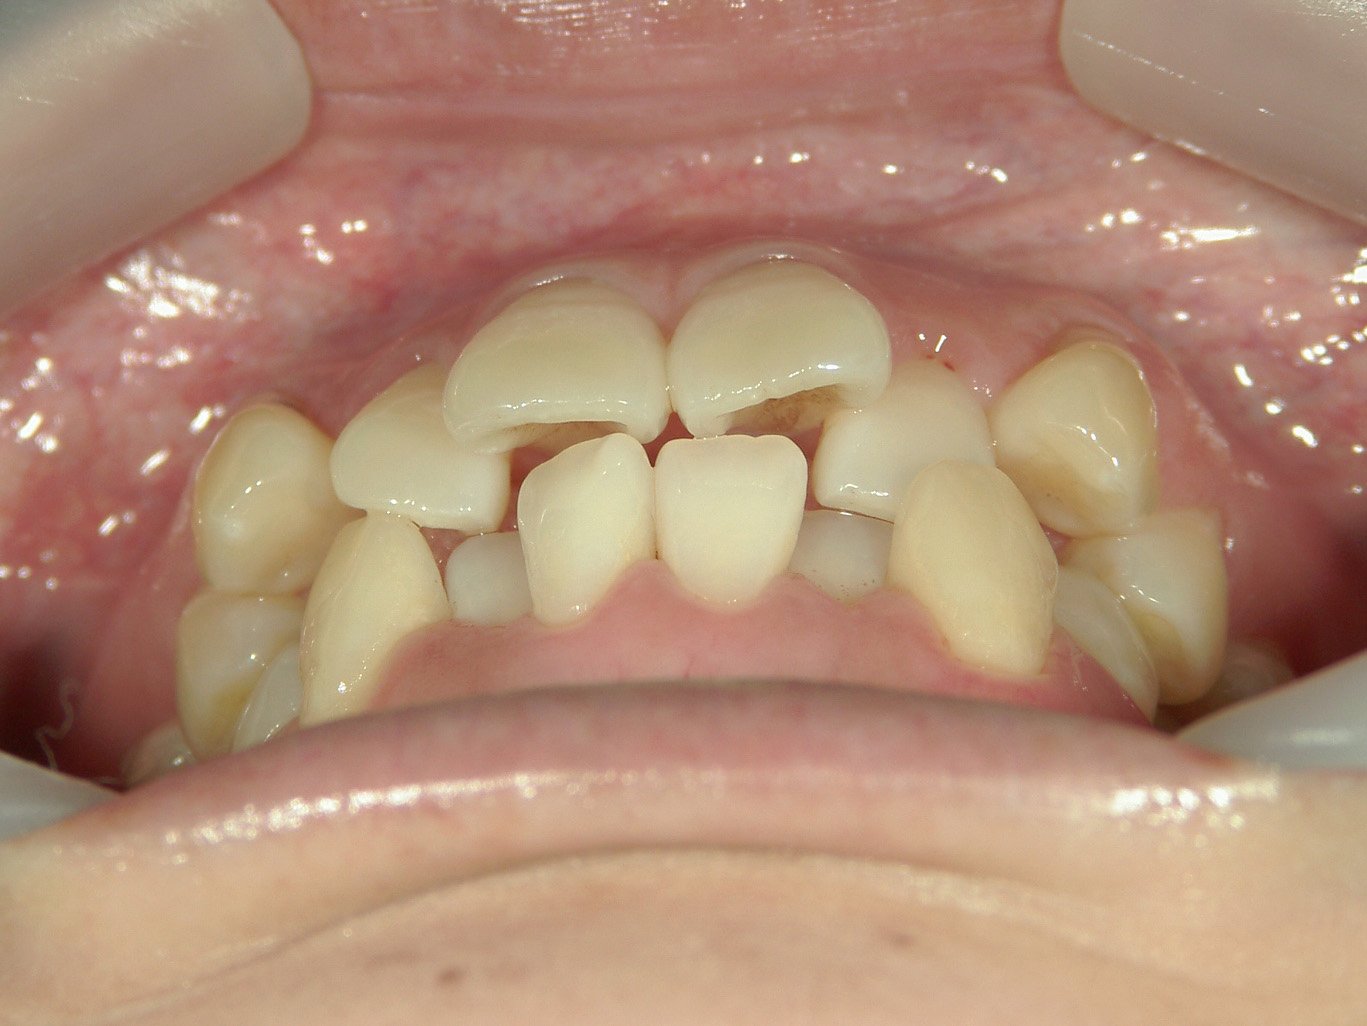

プチワイヤー矯正 症例(53)

主訴: 前歯の歯並びが気になる。

カテゴリー : ガタガタ(叢生)